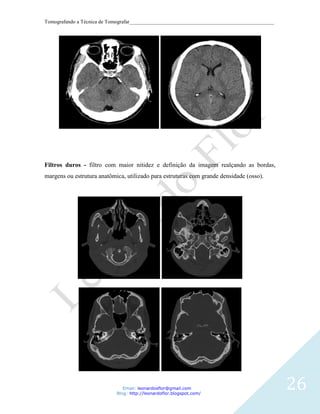

Filtros duros - filtro com maior nitidez e definição da imagem realçando as bordas,

margens ou estrutura anatômica, utilizado para estruturas com grande densidade (osso).